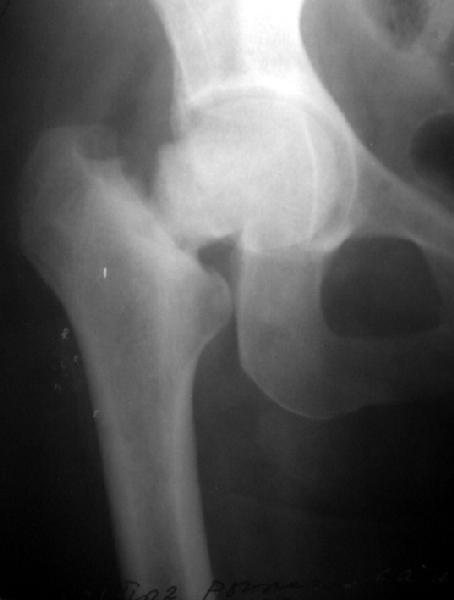

Женщина лет 40 переведена к нам из городской больницы с переломом шейки бедра.

Упала дома 5.11.02. С ее слов, в послдений год лечилась консервативно от якобы коксартроза с этой же стороны. Снимков не делали. Этот сустав болит последние несколько месяцев. На снимках обращает на себя "замыленность" краев. Не усталостный ли это перелом? Дама полноватая. Ограничения амплитуды движений до травмы она не отмечала.Мнения о тактике у нас разошлись в диапазоне от остеосинтеза винтами до эндопротезирования, с остеотомиями между ними. Помогите, пожалуйста, обосновать выбор.

Мне кажется с этой женщиной надо прежде всего хорошо поговорить. Перелом выглядит несвежим (не менее 4-6 месяцев) и не патологическим. Усталостный ведь тоже патологический! По-моему, был у неё импактный относительно устойчивый перелом шейки, образовавший фиброзный N-Union. Поэтому были у неё боли и "коксартроз". При последнем падении она его дез-импактировала.

To my eye, it does have a sclerotic edge to it, but it may just be projection. Does she have diabetes or other metabolic- eg renal problems? Jim Carr

The very clear ends and sclerosis suggest an osteitis. Difficult to tell re the hip but there appears to be sclerosis here in the acetabulum too. I would be very suspicious of Pagets. Does she have any metabolic bone

To me the whole head, neck and adjacent acetabular area look sclerotic.

Прилагаю еще одну рентгенограмму - обзорный снимок таза от 11 ноября, еще до перевода к нам. Ранее были посланы снимки, сделанные 13 ноября

уже у нас.

Думаю прежний снимок мало что меняет. Есть базо-цервикальный перелом, на мой взгляд, несвежий. Снимок 11.11.02 технически хуже 13.11.02 и сделан в несколько иной проекции. Жаль что в обеих случаях нет аксиального снимка шейки, на мой взгляд просто необходимого для диагноза.